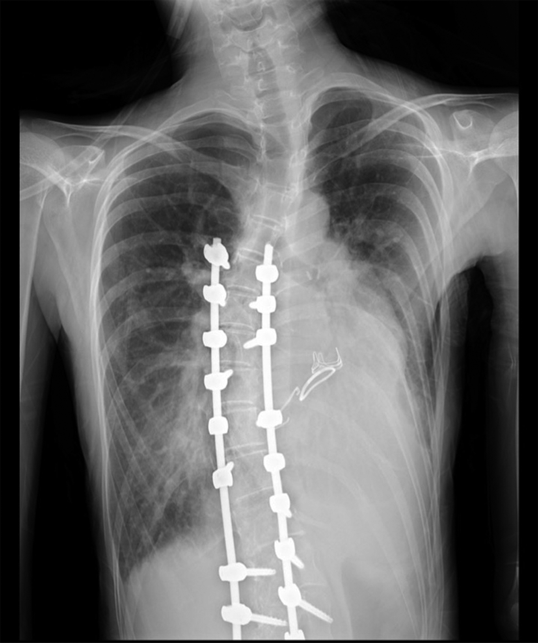

胸部レントゲン

心胸郭比63%,肺血管陰影増強と側弯を認めた(Fig. 1).

Fig. 1 Chest X-ray on admission